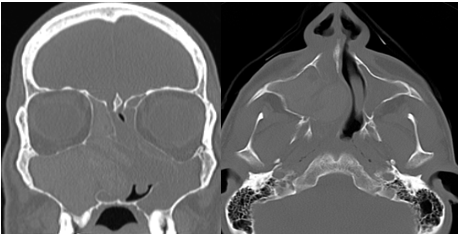

She consulted due to swelling and anesthesia in the cheek of several years of evolution and mild left exophthalmos. Rhinoscopy and nasal endoscopy revealed a reduction in the left nasal cavity due to medial displacement of the medial wall of the maxillary sinus. Computed tomography (CT) revealed an expansive lesion in the left maxillary sinus with bone erosion of all its walls. The tumor was in contact with the inferior and lateral rectus muscles and extended to the pterygomaxillary fossa (Figure 1).

Figure 1 Coronal and axial CT: an expansive lesion is observed in the maxillary sinus with erosion of the bony walls and displacement of the eyeball.